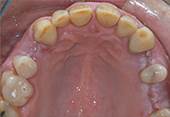

Ausgangslage: Der Patient wünscht sich nach Jahren der Zahnlosigkeit im Oberkiefer einen festsitzenden Zahnersatz. Der Knochenabbau ist noch -

Die mit einem speziellen Verfahren hergestellte Chirurgieschablone ermöglicht eine sehr atraumatische Chirurgie (ohne Aufklappung der -

Schlusssituation: Die gute Positionierung der Implantate ermöglichte die Herstellung einer verschraubten, festsitzenden